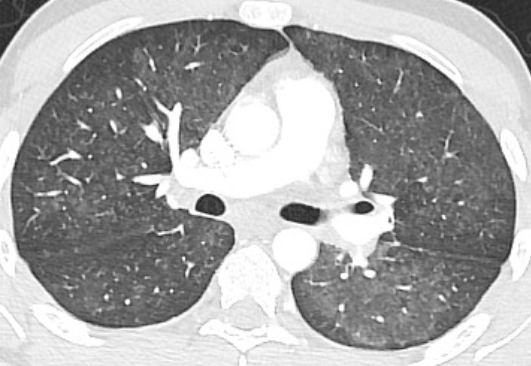

——そして胸部CT——

もろもろ検査→電子タバコの肺障害と診断!